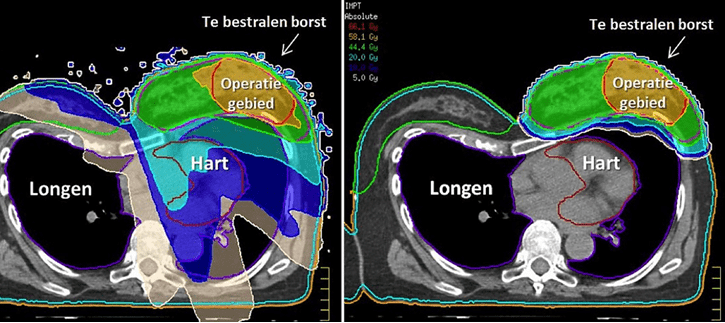

4. Beoordeling of planvergelijking

Bij model-based indicaties maken we een planvergelijking tussen fotonen- en protonentherapie. Bij highly likely indicaties verwijst u de patient direct voor intake naar HollandPTC. Gelijktijdig wordt in HollandPTC en het verwijzend instituut een klinisch uitvoerbaar fotonen- en protonenplan gemaakt en vergeleken. Dit zorgt voor een kortere doorlooptijd.